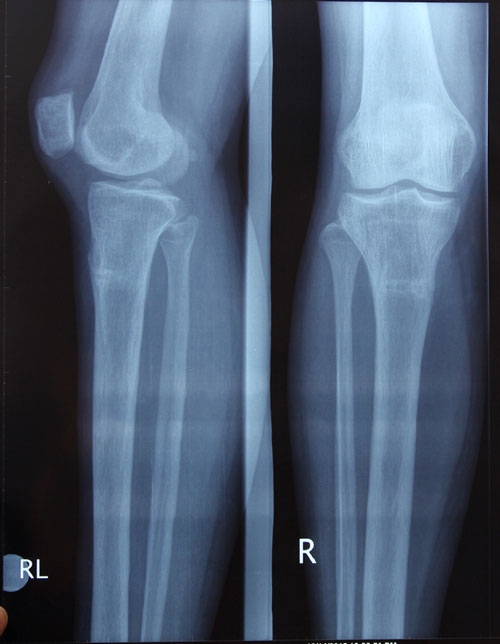

Рентген в 90 дней.

Приезжайте на снятие аппаратов!

foto-2.jpg

foto.jpg